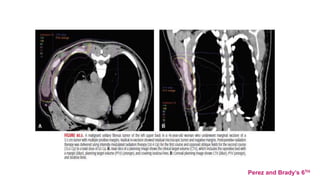

CT MRI(T1)

Perez and Brady’s 6TH

MRIScanvs CTScan(Demas et al. compared MRI and CT for STS lesions in the

extremity and reported that for 23% of cases, the MRI scans showed tumor

CT MRI(T1) Perez andBrady’s 6TH MRIScanvs CTScan(Demas et al. compared MRI and CT for STS lesions in the extremity and reported that for 23% of cases, the MRI scans showed tumor involvement in muscles that appeared normal on CT scan)